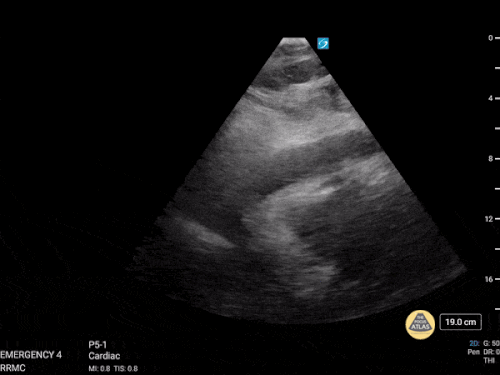

VCI (İnferior vena cava)

• IVC / Subkostal pencere